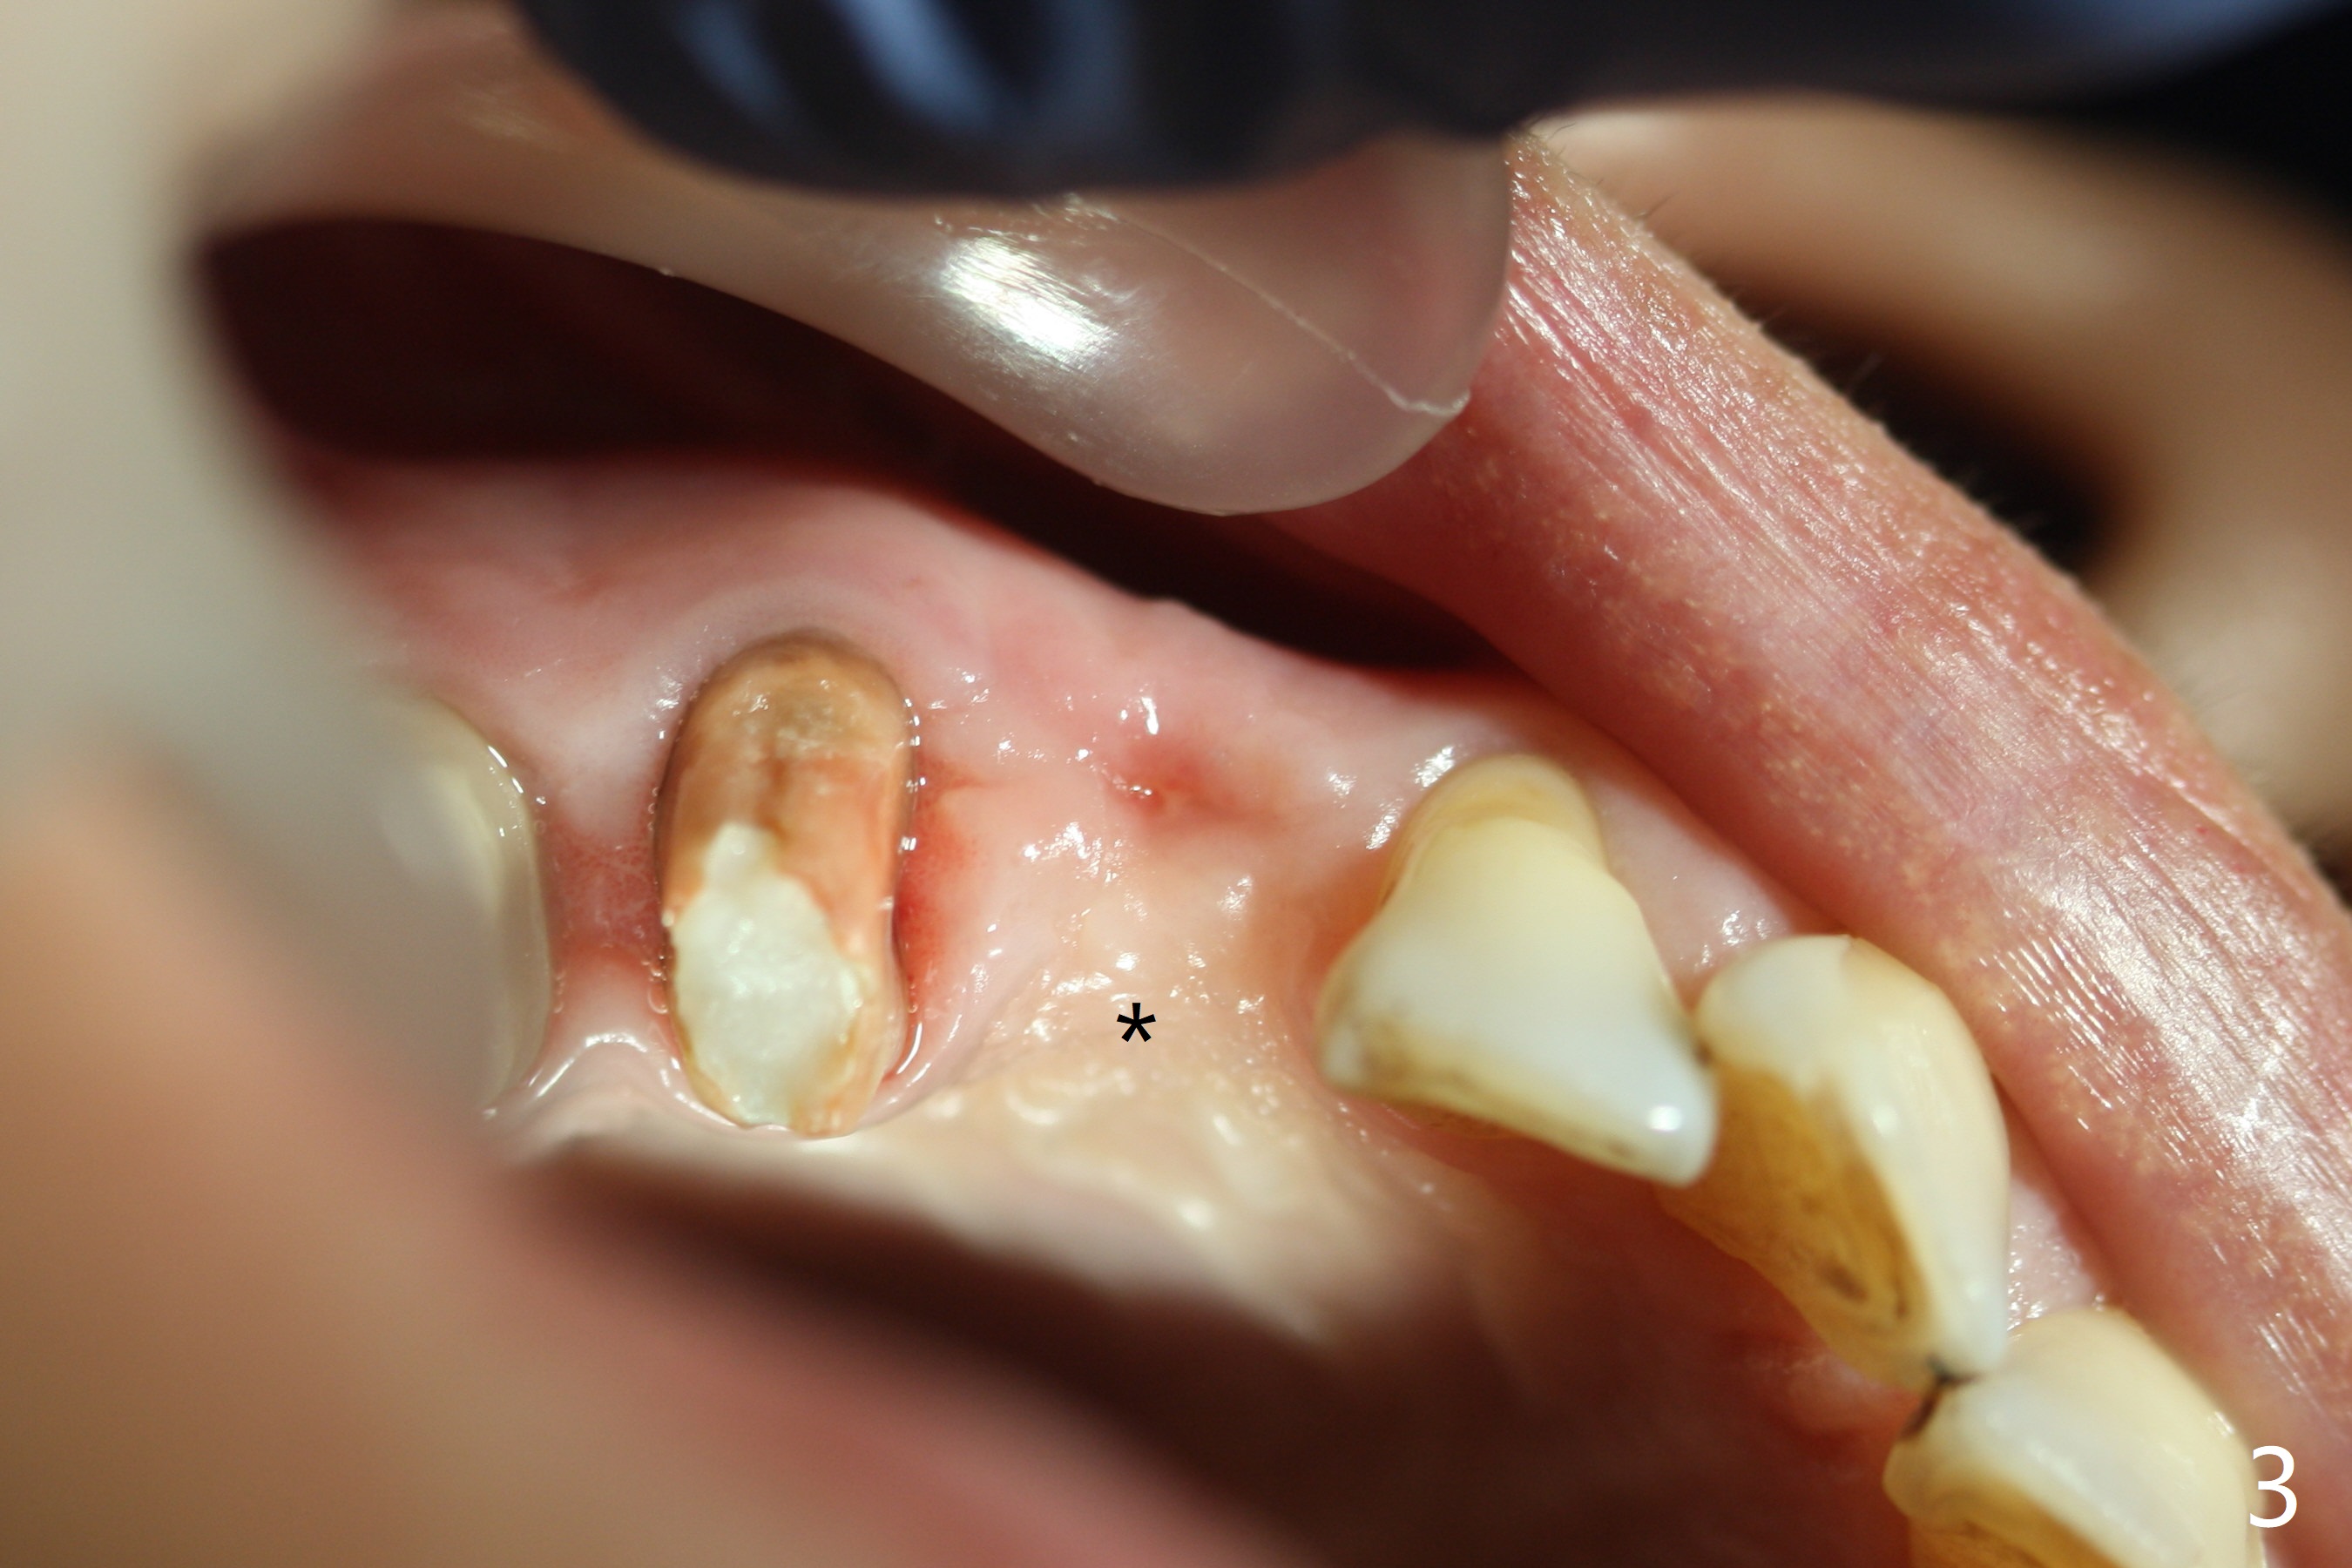

A 60-year-old woman returns for CT 4.5 months post implant removal at #6 (Fig.1). The ridge remains narrow and short because of the impacted tooth. The latter appears necessary to be extracted for a longer implant (12 or 14 mm vs. 10 mm). To accommodate a larger implant (2.5 mm vs. 2.0 mm), prepare DIO bone expander kit. But first, use an initial drill from IS Mini implant kit, followed by a parallel pin for trajectory and occlusal check. Take intraop CBCT if needed. Osteotomy will be initiated palatal (Fig.3 *, as compared to the previous osteotomy (Fig.2 <)). To reduce palatal implant thread exposure, use an implant with 4 mm cuff and place bone graft/collagen membrane. At first take impression with Alginate for wax up. In fact the stent is available. Instead PVS impression is taken for guide. The latter will be used to start initial osteotomy (2.2 mm drill for a few mm (4)), followed by 1.2 mm drill for depth.